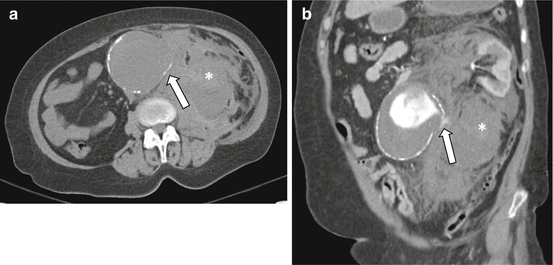

Fig. 7.1

Ruptured abdominal aortic aneurysm. Noncontrast transaxial (a) and contrast-enhanced coronal (b) CT images demonstrate the “tangential calcium” sign with focal disruption of intimal calcification which points at a tangent from the expected aortic circumference (a, arrow). Also note the contained active extravasation (b, arrow) and the large left-sided retroperitoneal hematoma (*)

Focal discontinuity of intimal calcification within an AAA wall, particularly when shown to be a new finding in comparison with prior studies, has been shown to be a useful sign of acute or impending rupture [9]. The “tangential calcium” sign, defined as calcified atherosclerotic plaque adjacent to an area of focal calcium discontinuity that is divergent from the normal arc of the aorta, is another finding highly associated with AAA rupture (Fig. 7.1) [13].